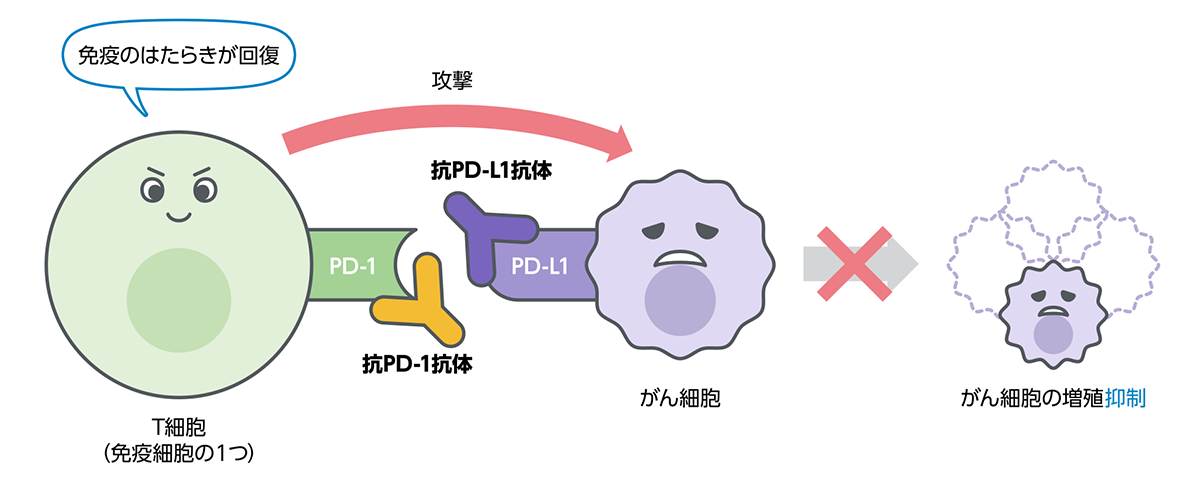

免疫療法のために行うPD-L1検査

免疫の働きにブレーキをかける仕組みの1つが「免疫チェックポイント」と呼ばれる分子であり、「PD-1」はその1つです。「PD-L1」はPD-1と結合し、PD-1を活性化させる働きを持つ、細胞表面に存在するタンパク質です。がん細胞の中には、このPD-L1を細胞の表面に出すことによって、免疫の働きから逃れているものがあると考えられています。

免疫のブレーキを解除する治療とPD-L1検査

免疫の働きへのブレーキを解除し、体が本来もつ免疫の力でがんと戦うという治療法が免疫チェックポイント阻害療法です。肺がんでは、PD-1とPD-L1の結合を妨げてブレーキを解除する免疫チェックポイント阻害療法が実用化されています。肺がん細胞の表面にPD-L1がどの程度発現しているかを調べるのがPD-L1検査です。

また近年、がん治療としてがん免疫療法が注目されており、その中でPD-L1という物質が着目されています。肺癌診療ガイドライン2021年版において、遺伝子検査とともにPD-L1検査もおこない、その結果に基づいて治療戦略を考えることが記されています。

なお、PD-L1検査は保険で認められています。